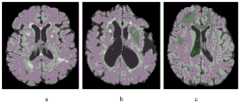

图10标准化后的训练样本和测试样本的横向切片;a.训练样本,b.测试样本#1,c.测试样本#2;Figure 10. Horizontal slices of normalized training samples and test samples; a. training sample, b.

分别使用公式(4)和(5)对训练样本和测试样本进行线性归一化,然后,令max_intensity_range=255,并分别使用公式(6)和(7)对线性归一化后的训练样本和测试样本进行强度转换,图10是与图2相对应的转换后的结果。图11是三个样本的直方图曲线,从图11可以看出,强度标准化处理后,直方图曲线形态和波峰位置基本接近。Use formulas (4) and (5) to linearly normalize the training samples and test samples, respectively, then, let max_intensity_range=255, and use formulas (6) and (7) to linearly normalize the training samples and The test samples were subjected to intensity conversion, and Figure 10 is the converted result corresponding to Figure 2 . Fig. 11 is the histogram curve of the three samples. It can be seen from Fig. 11 that after the intensity normalization process, the shape of the histogram curve and the position of the wave peak are basically close.